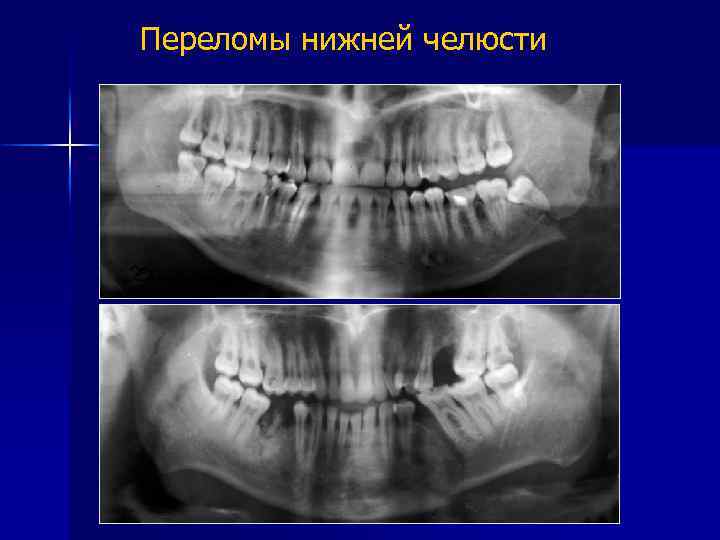

Переломы костей нижней зоны лица

Схема переломов нижней челюсти 1 – шейки мыщелкового отростка 2 – основания мыщелкового отростка 3, 4, 5 – задне -, средне - и переднеугловые 6 – подбородочный 7 – срединный

Переломы нижней челюсти в области: угла нижней челюсти - 57 -65% мыщелковых отростков - 21 -24% премоляров и клыков - 16 -18% моляров - 14 -15% Бернадский Ю. И. , 1999 г.

Переломы нижней челюсти

Ортопантомограмма. Переломы нижней челюсти в области мыщелкового отростка справа, в зоне 4. 7 и 3. 3 зубов со смещением костных фрагментов. Челюсти шинированы.